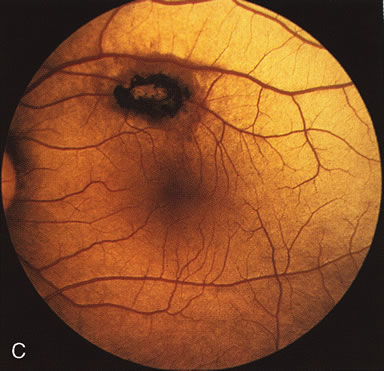

PIGMENT PATTERN DYSTROPHIES

The fundus abnormalities in pigment pattern dystrophies may be subtle, especially when the pigmentary changes are orange and yellow in color. However, FA is most dramatic in highlighting these abnormalities. Thus, FA will confirm, and in some circumstances provide, the diagnosis (Fig. 11AE). Although there is no histopathologic confirmation, the fundus and angiogram suggest that an abnormal deposition of lipofuscin in the RPE is responsible for the clinical picture.

Fig. 11. Pigment pattern dystrophies. Subtle changes of the fundus in this family member with a pattern dystrophy (A) are highlighted on angiography (B). Equally dramatic is the fluorescein angiography of this young woman who presented with poor vision in association with a retinal hemorrhage (C). The angiogram reveals a bilateral, symmetric reticular pattern of the posterior pole (D, E).